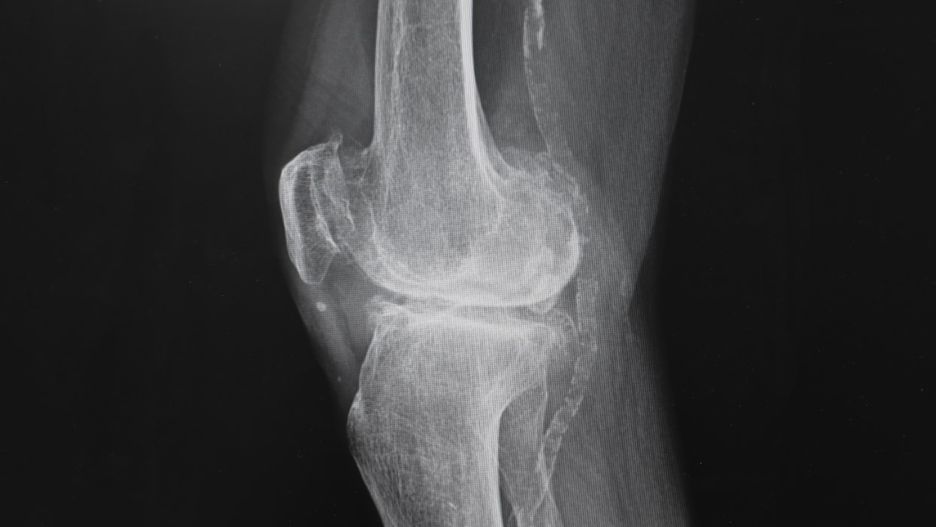

Jałowa martwica kości to schorzenie, w przebiegu którego fragment tkanki kostnej obumiera.Jałowa martwica kości to schorzenie, w przebiegu którego fragment tkanki kostnej obumiera.

Źródło zdjęć: © Adobe stock

Jałowa martwica kości u dzieci i dorosłych jest patologią, istotą której jest obumieranie fragmentów tkanki kostnej bez udziału patogenów, to jest bakterii, wirusów czy pasożytów. W miarę rozwoju choroby tkanka martwicza wchłania się, po czym jest zastępowana przez odbudowującą się tkankę kostną. Ta jednak nie jest pełnowartościowa, stąd podatna na deformacje.